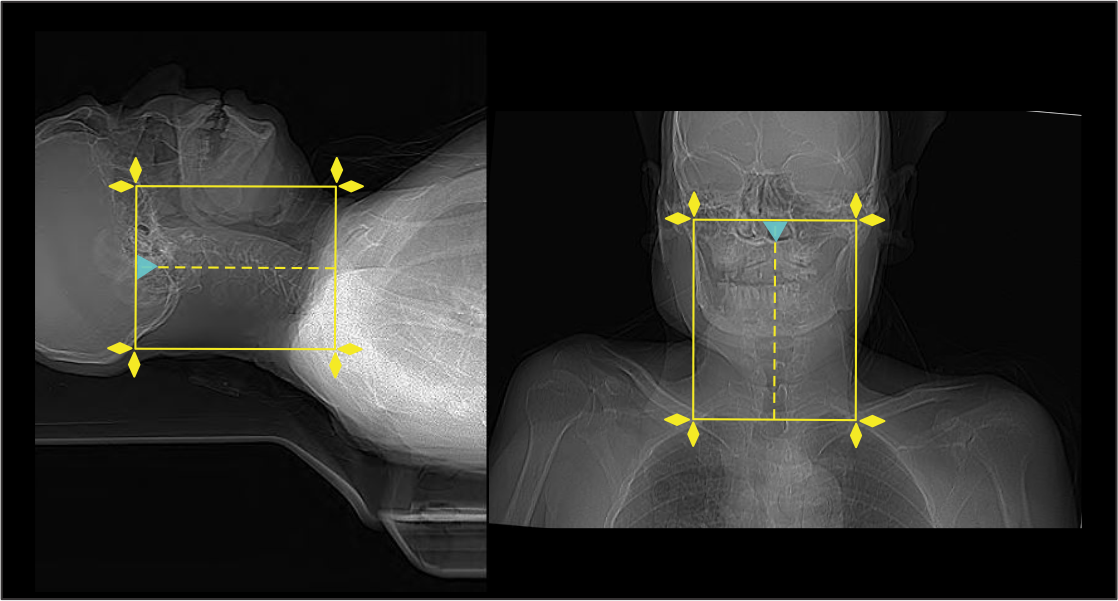

Patient positioning

- Position the patient in head-first, supine and in the iso-center.

- Keep shoulders in a pulled down position and arms next to the body.

Explanation: this reduces streak artifacts or beam hardening artifacts due to wide shoulders. Placing a cushion under mid-upper thorax moves shoulders posteriorly, and helps to reduce streak artifacts at the root of the neck.

- Plan the scan start point at the level of clavicles and set scan direction outward the gantry.

Scan planning

- Plan the scan slab to cover from skull base (or C1) to first thoracic vertebra (T1).

- Reduce the field of view (FOV) as small as appropriate.